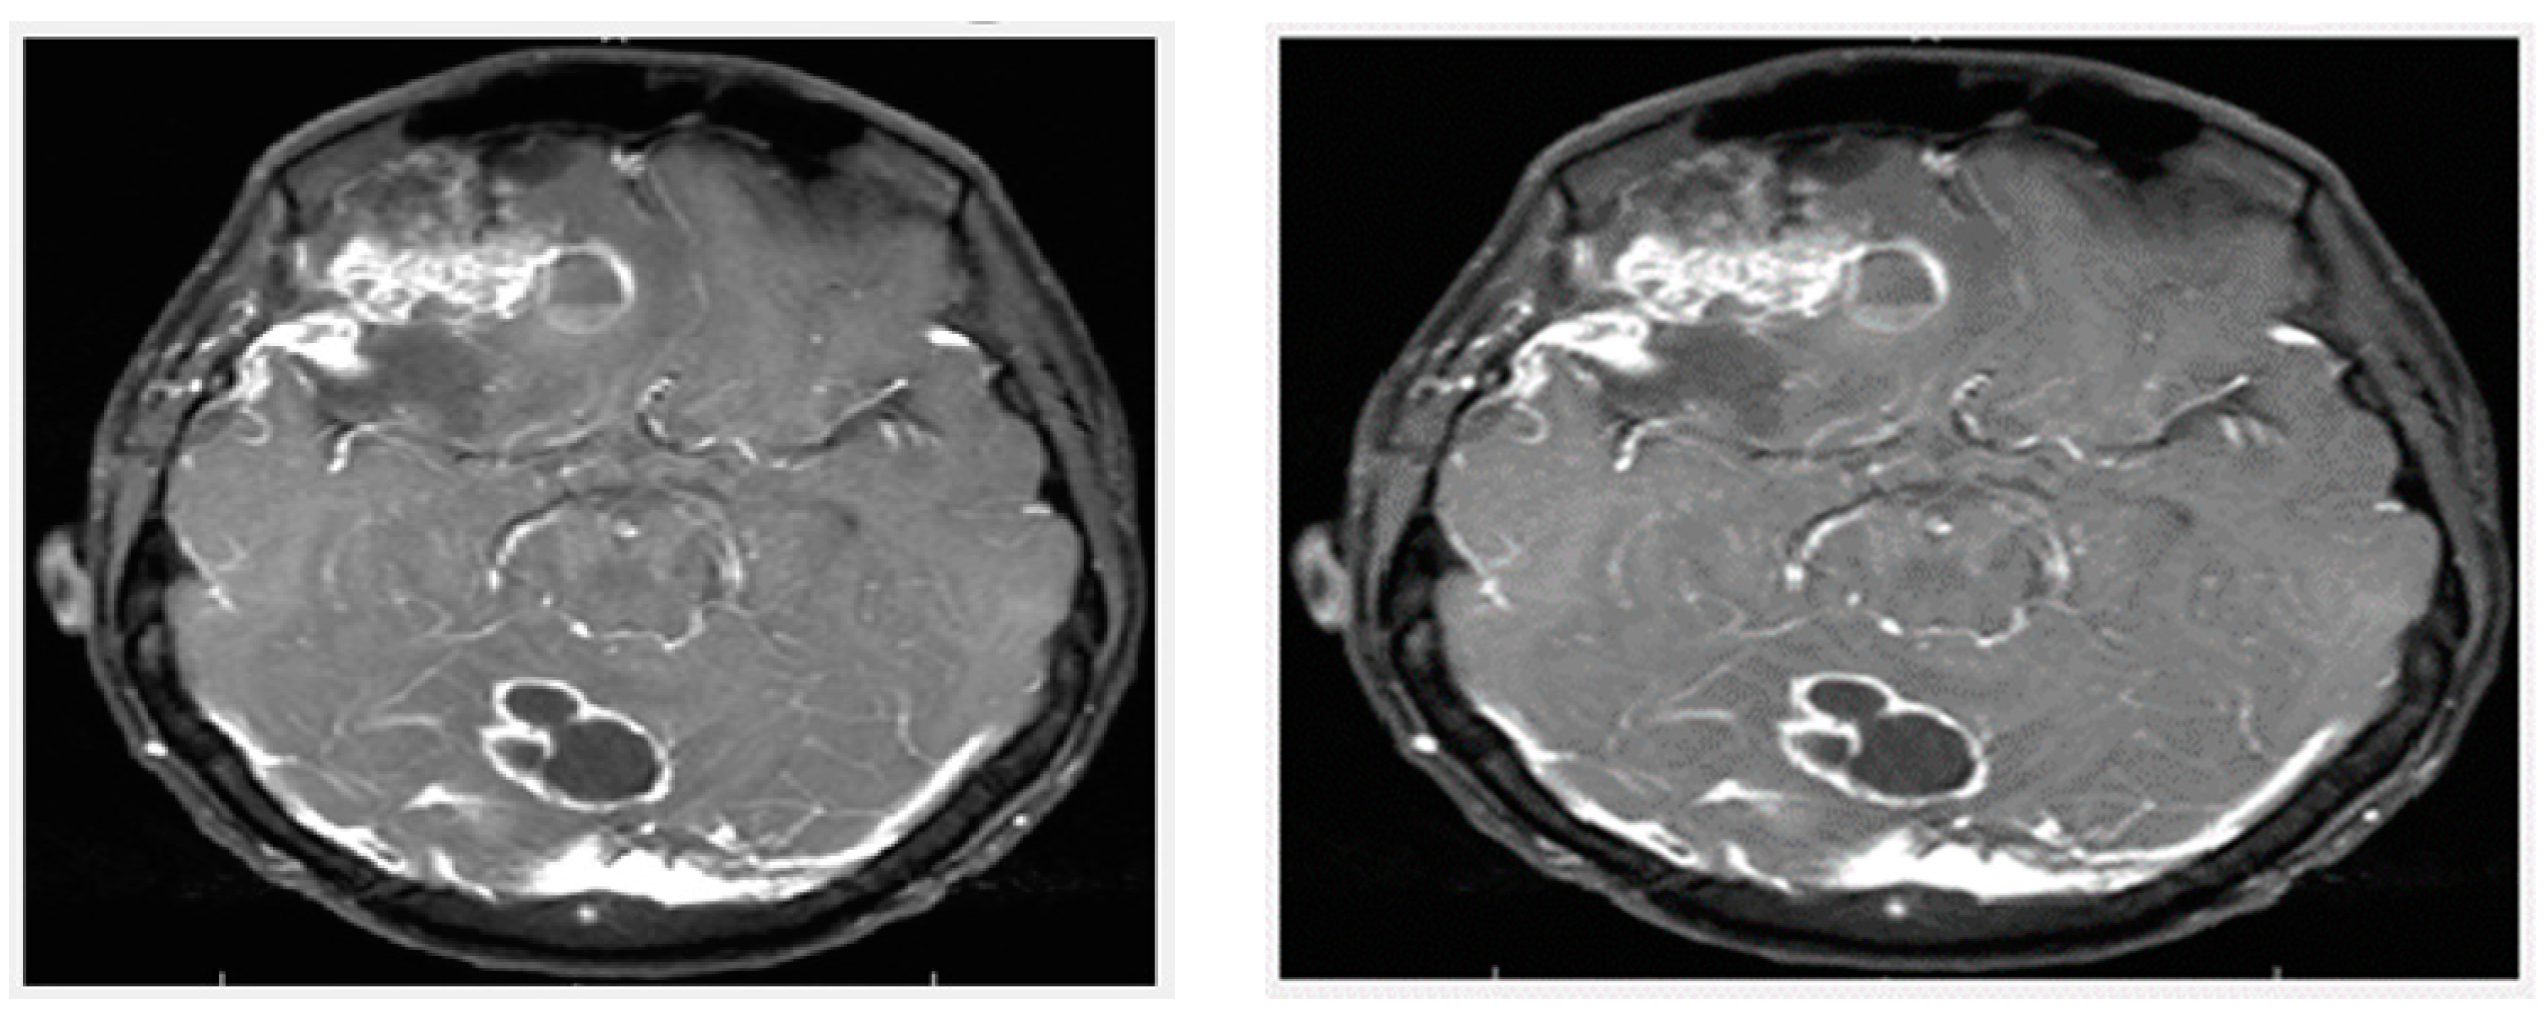

3.3. Preprocessing

In the preprocessing step, image enhancement is used as the first step. In this study, a contrast stretching filter was used for the enhancement of an MRI image for this greyscale image, since it functions relatively better. Without distorting the relative grey level intensities, the contrast stretching filters improved the contrast of an image [12]. As a consequence, an enhanced image does not offer an unnatural look like the equalization of histograms. Via contrast stretching, the image contrast is enhanced by stretching the spectrum of contrast values to spam the target scale from 0’s to 1’s. The uncertainty which can occur in the regions of images has been removed by contrast stretching enhancement. For this analysis, Figure 5 demonstrates the performance of a contrast-stretching-based enhancement test image.

Figure 5.

MRI image after preprocessing: (Left) Original image and (Right) Enhanced image.